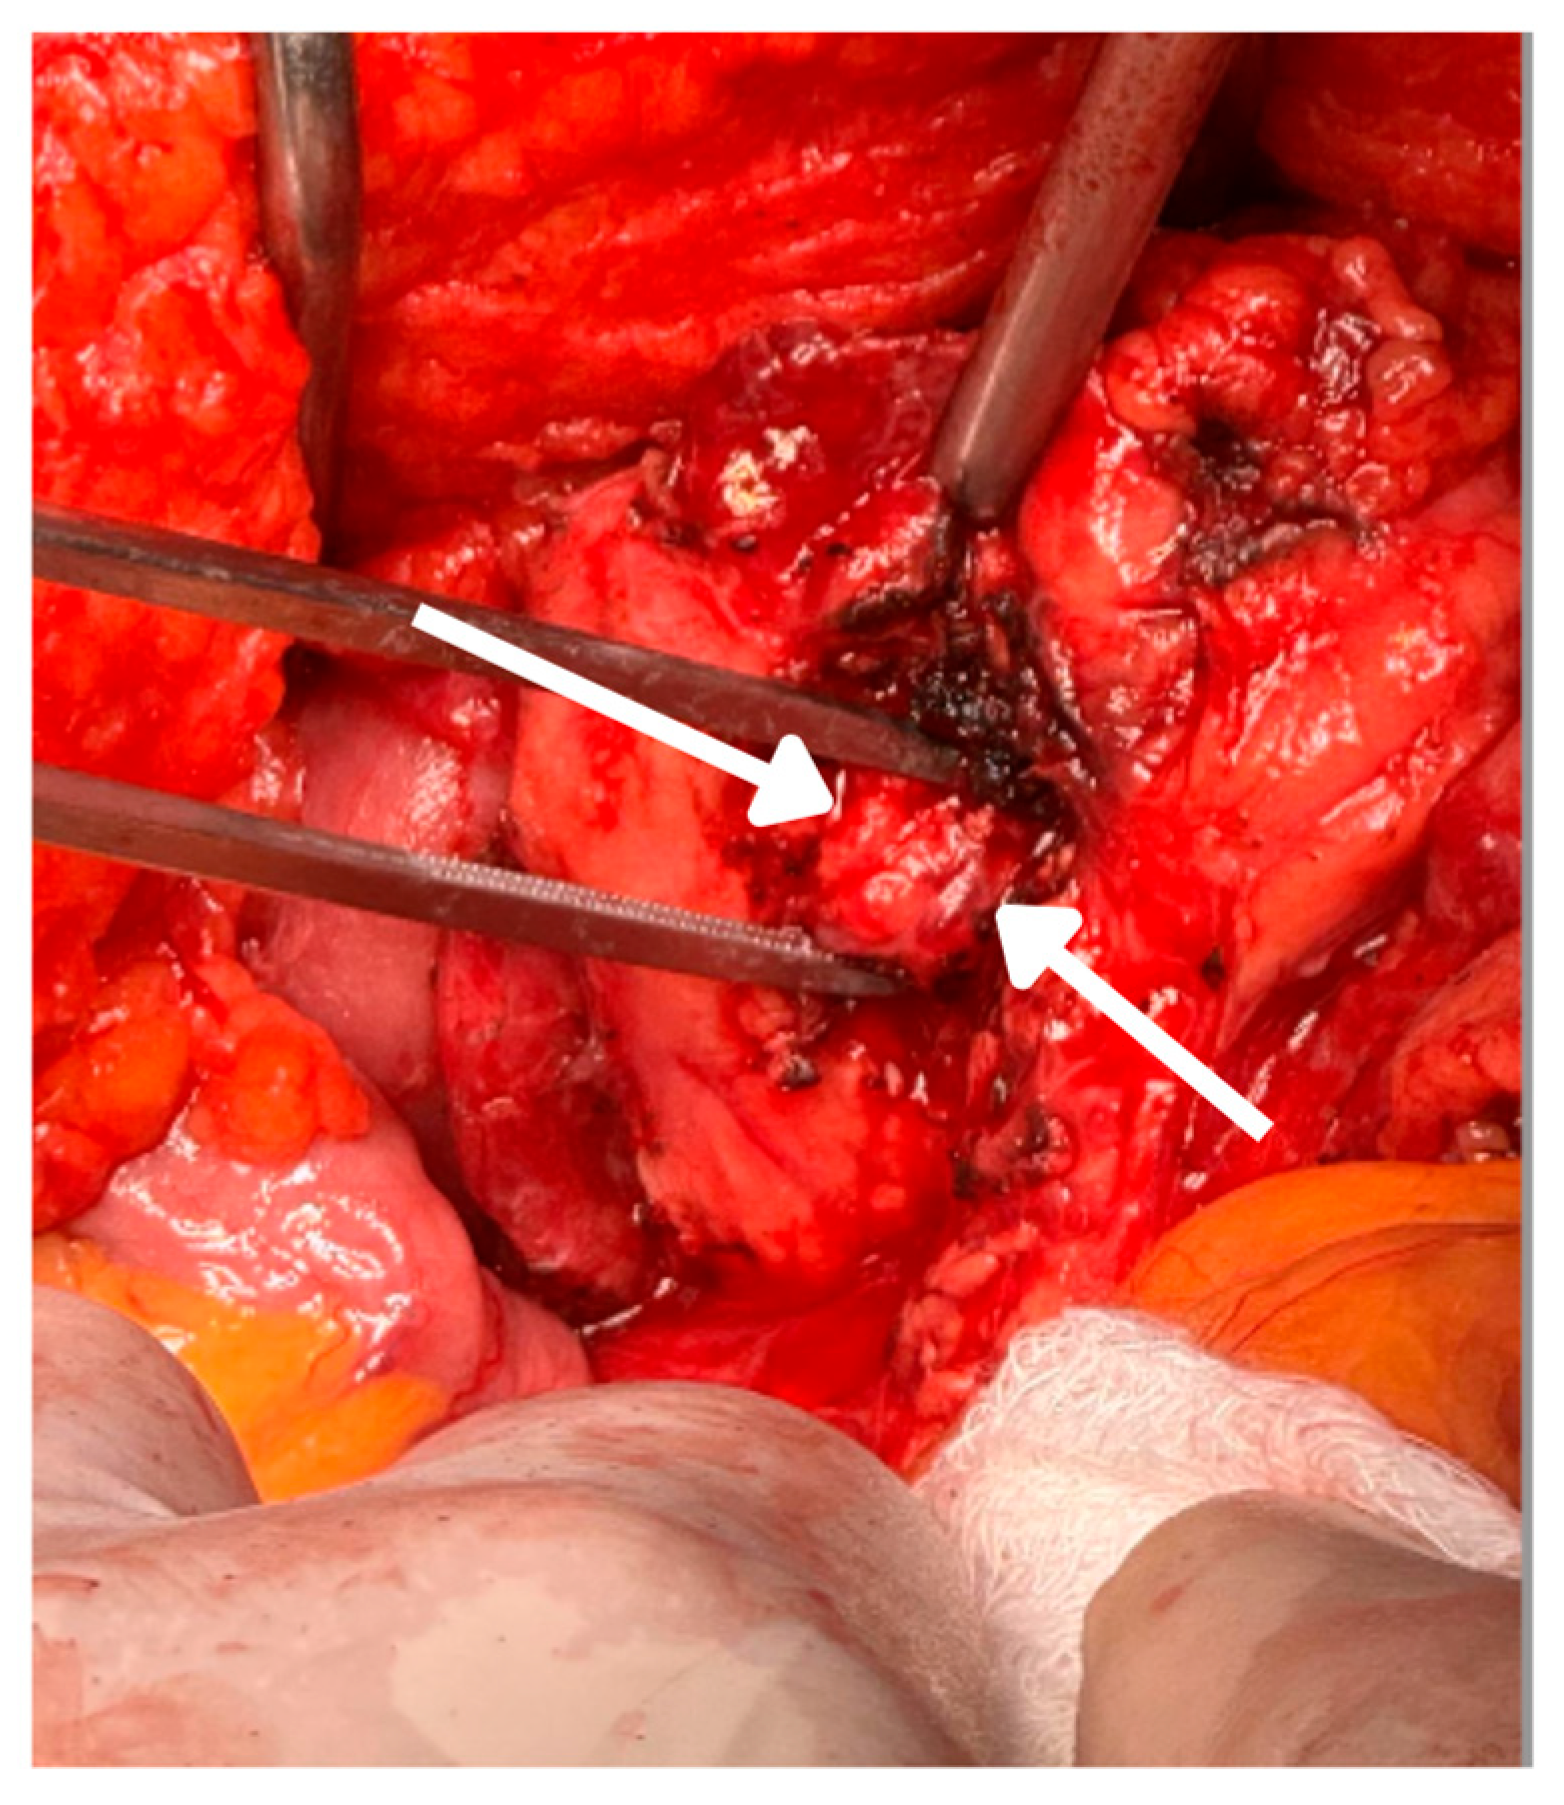

2.4. Surgical Intervention and Intraoperative Findings